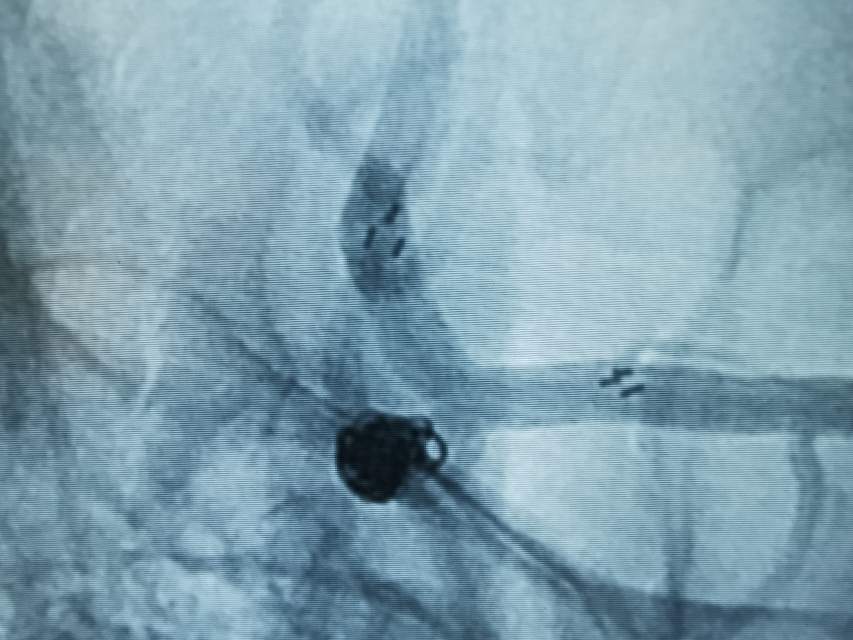

破裂的大脑中动脉动脉瘤二期支架植入

患者,中年男性,颅内动脉瘤破裂出血,急性期给予单纯弹簧圈大部致密栓塞(瘤颈少许残留),降低了急性期破裂出血的风险,急性期免除了使用抗血小板的顾虑和担心(如果使用支架),为了预防远期的复发,二期植入支架,就会安全多了